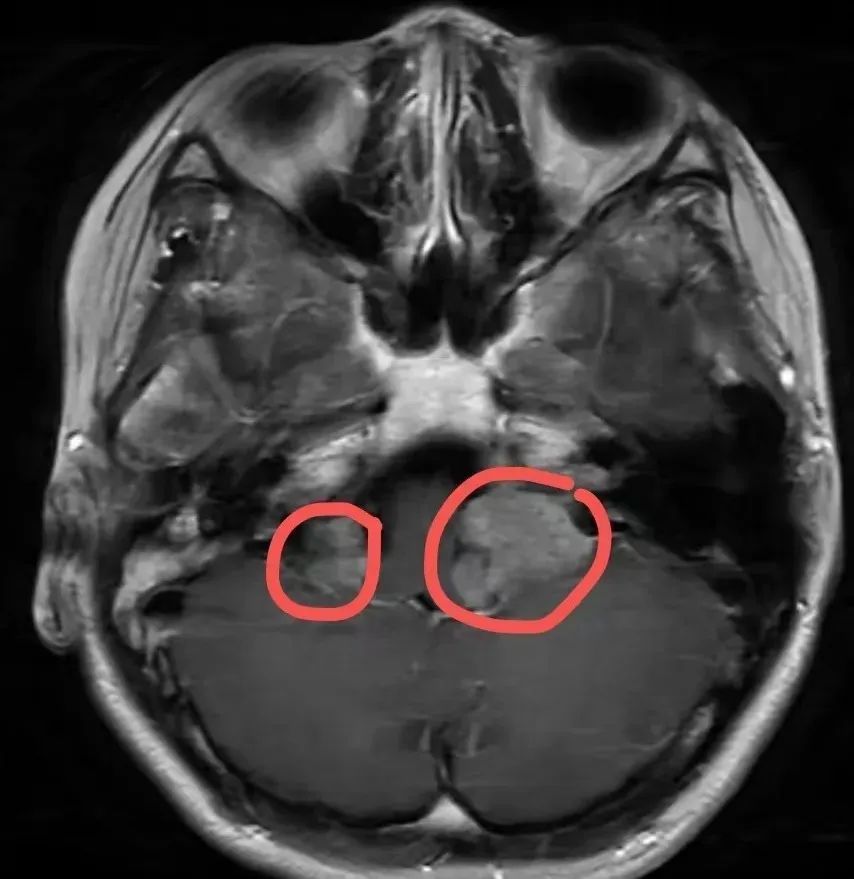

小叶双侧颅内的前庭神经

正被一种肿瘤“侵袭”

这即是她听力下落的元凶

历程抽象评估,医师合计,小叶右侧的听神经瘤当今较为踏实,可秉承按期随访不雅察。而左侧听神经瘤体积较大,对周围组织产生彰着压迫,导致小叶可能出现颅内高压等症状,将严重影响生计质料。